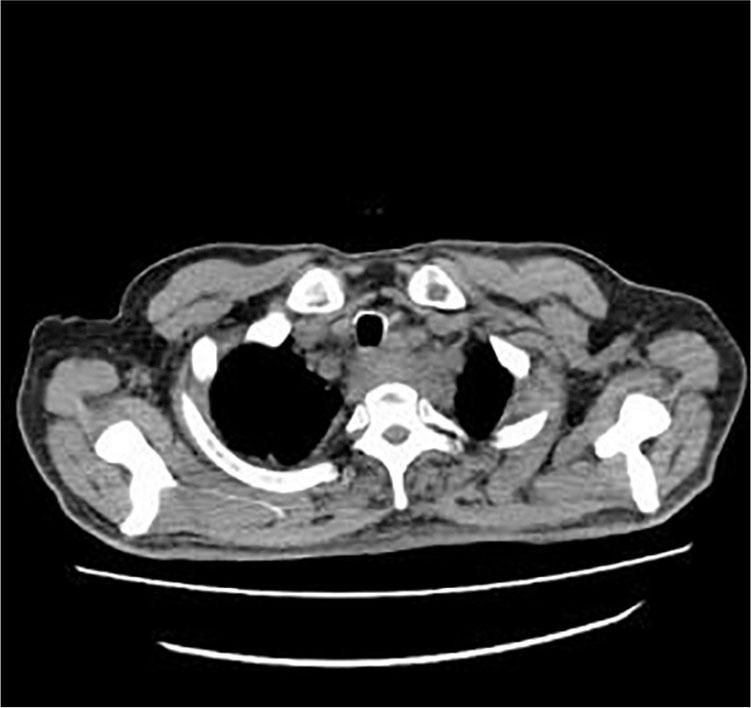

On September 23, 2016, a 56-year-old man consulted the emergency department for 7 days with unknown fever. The highest temperature was 38.5°C. Blood tests were as follows: WBC 7.75 × 109/L, NEUT 76.94%, CRP 120.57 mg/L, and procalcitonin 0.325 ng/ml. Posterior superior mediastinal masses with thickened adjacent esophagus wall and bilateral pleural effusion were revealed by thoracic computed tomography (CT) scan (Figure 1). A 1.0 cm × 2.0 cm protuberant mass was found in the left wall of the esophagus at 20 cm from the incisors by the gastric endoscopy (Figure 2). Endoscopic biopsy shows a chronic active inflammation with ulcer and granulation tissue proliferation. Examine the medical history in detail at that moment, the patient was diagnosed with an odynophagia and admitted that he had accidentally swallowed a fishbone 2 months ago. Taken together, the patient was diagnosed with secondary mediastinitis due to esophagus perforation caused by the ingestion of fishbone. The patient had been treated moxifloxacin intravenously for 15 days, and then he was discharged without fever. Obvious back pain and decreased muscle strength began on the 7th day after discharge. On November 10, he had a Magnetic resonance (MR) of the thoracic vertebra, and the result was C7/T1 centrum infection and paravertebral abscess (Figure 3). The surgical intervention had been performed 4 days later. Consequently, the back pain disappeared, the muscle strength recovered, and an MR reexamination showed the patient recovered completely (Figure 4).

Figure 1

The CT scan result.